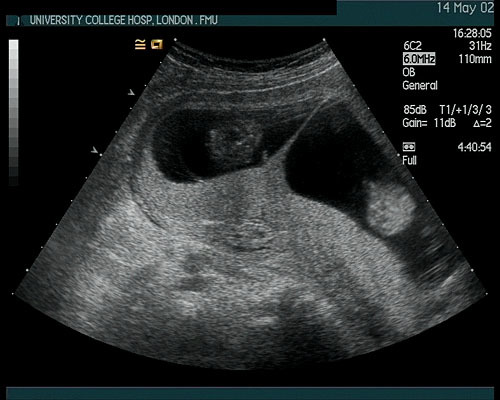

Most common location of ectopic pregnancies

95+% in the fallopian tubes

-majority of which are in the ampulla

Location where an ectopic pregnancy would last the longest

Cornual/interestitial = part of the fallopian tube that is directly attached to the cervix and is even surrounded by myometrium

=> has the support/strength of the myometrium to allow for expansion